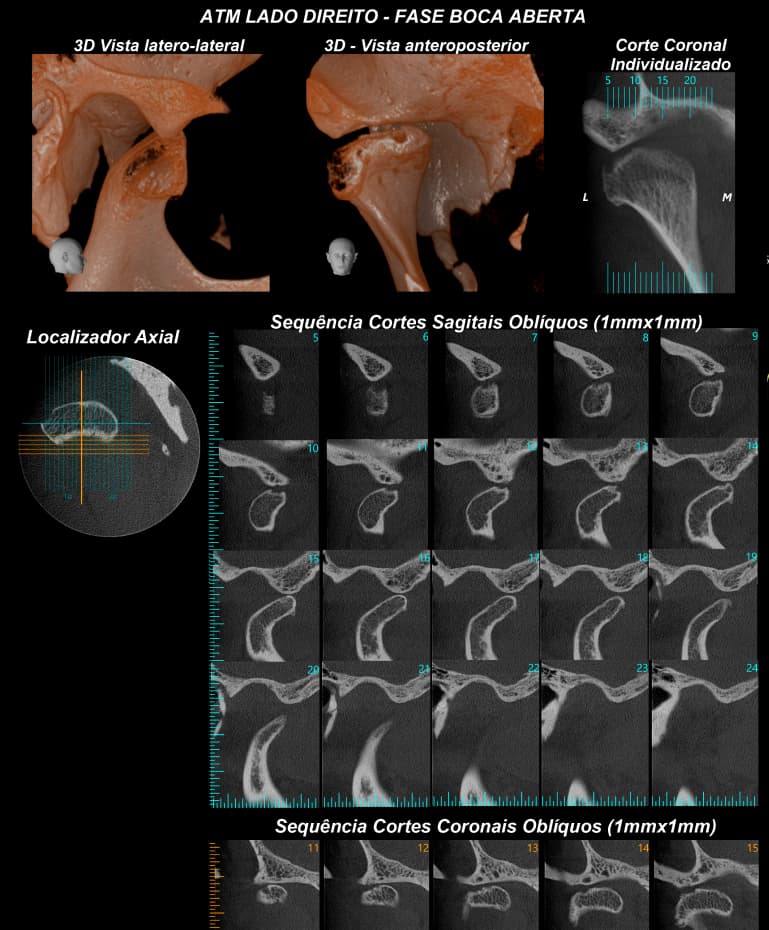

TOMOGRAFIA COMPUTADORIZADA DE ALTA RESOLUÇÃO por feixe Cone Bean - MORITA X800

• ATM´s